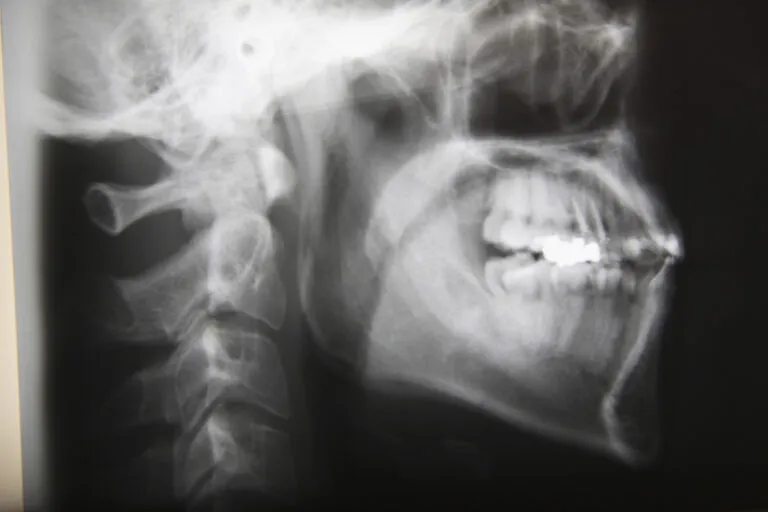

インプラント治療は、顎の骨に人工の歯根を埋め込む外科的な処置を伴う治療であるため、安全性や正確性が非常に重要になります。当院では、口腔外科分野に精通した歯科医師がインプラント治療を担当し、専門的な知識と経験をもとに、患者様一人ひとりの状態に合わせた治療を行っています。口腔外科は、歯や歯ぐきだけでなく、顎の骨、神経、血管など、お口まわりの構造を総合的に診る分野であり、インプラント治療においても、これらを正確に把握することが欠かせません。特に、顎の骨の状態が複雑な場合や、神経や血管が近接しているケース、過去に外科処置を受けた経験がある方などでは、より慎重な診断と治療計画が求められます。当院では、事前に各種検査を行い、インプラント治療が可能かどうかを丁寧に判断するとともに、治療の流れや考えられるリスクについても分かりやすくご説明します。また、持病をお持ちの方や全身状態に配慮が必要な方についても、状況を確認しながら無理のない治療計画を検討します。すべての方に同じ治療を行うのではなく、安全性と長期的な安定を重視したインプラント治療を心がけている点が当院の特徴です。外科処置に不安を感じている方や、インプラント治療について詳しく知りたい方も、まずは安心してご相談ください。

日本口腔外科専門医とは、日本口腔外科学会が定める厳格な基準を満たし、口腔外科分野において高度な知識と経験を有すると認定された歯科医師のことを指します。口腔外科は、歯や歯ぐきの治療にとどまらず、顎の骨、口腔内の粘膜、神経、血管、顎関節など、お口まわり全体を対象とする専門分野であり、外科的処置を含む幅広い診療に対応することが求められます。日本口腔外科専門医の認定を受けるためには、一定年数以上の臨床経験を積み、多くの症例を経験したうえで、学会が定める研修や試験に合格する必要があります。また、専門医資格は一度取得すれば終わりではなく、継続的な研鑽や学術活動を通じて、最新の知識と技術を維持していることが求められています。そのため、日本口腔外科専門医は、外科的な判断力や安全管理に関する知識、全身状態を考慮した治療計画の立案などにおいて、専門性の高い視点を持っているとされています。インプラント治療においても、顎の骨の状態や神経・血管の位置を正確に把握し、リスクを考慮したうえで治療を進めることが重要であり、口腔外科分野に精通した歯科医師が担当することで、より慎重で的確な判断が期待できます。ただし、専門医であってもすべての治療が必ず成功するというものではなく、患者様一人ひとりの状態に合わせた診断と十分な説明が欠かせません。日本口腔外科専門医とは、専門的な知識と経験を背景に、安全性と適切な治療を重視する歯科医師であり、外科的処置に不安を感じている方にとって、一つの安心材料となる存在といえるでしょう。

インプラント治療は、顎の骨の状態や噛み合わせ、全身の健康状態など、さまざまな要素を総合的に判断したうえで進める必要がある治療であり、治療を担当する歯科医師の知識や経験が重要な役割を果たします。当院では、インプラント治療に関する専門的な知識を有し、これまで多くの症例に向き合ってきた歯科医師が治療を担当し、患者様一人ひとりの状態に合わせた丁寧な診療を行っています。インプラント治療では、事前の診断や治療計画の立案が結果に大きく影響するため、顎の骨の形や量、神経や血管の位置、噛み合わせのバランスなどを細かく確認し、慎重に判断することが欠かせません。経験を積んだ歯科医師であれば、こうした情報を踏まえたうえで、想定されるリスクや注意点を把握し、無理のない治療計画を立てることが可能になります。また、治療中だけでなく、治療後の経過やメンテナンスまで見据えた対応ができることも、経験の積み重ねによる強みの一つです。当院では、技術だけを重視するのではなく、患者様のお話を丁寧に伺い、不安や疑問に向き合いながら治療を進めることを大切にしています。インプラント治療に不安を感じている方や、他院で難しいと言われた経験がある方にとっても、まずは安心して相談できる環境を整え、専門的な視点から適切な判断をご提案することが、当院の役割であると考えています。